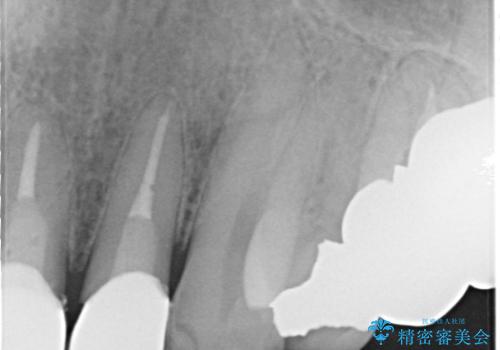

レントゲンを撮影すると、適合不良のかぶせ物が装着されており、根の治療も不十分であることが確認されました。